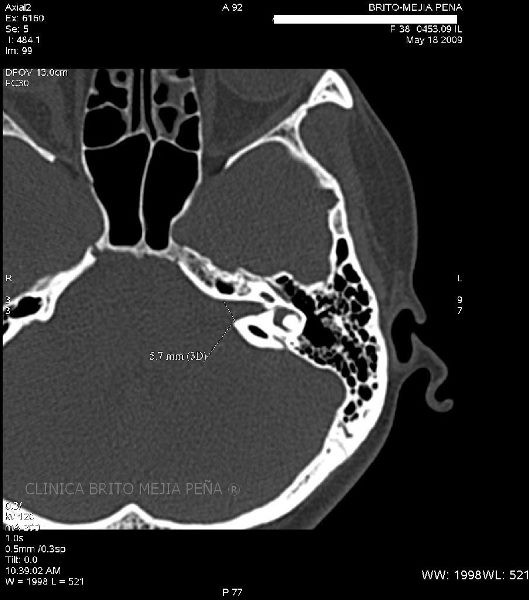

Cabeza y Cuello 2

Envíado por BMP Imágenes Diagnósticas

BMP Imágenes Diagnósticas